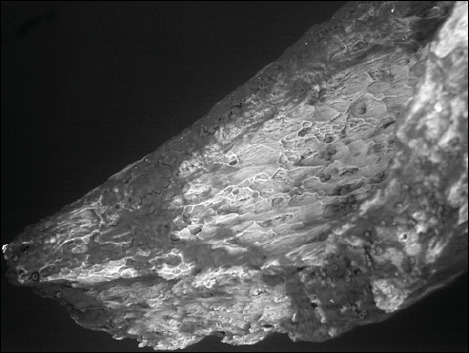

Results: The concentration of Ca2+ in the study group was significantly lower in the area of the anterior crus of the stapes than in the posterior crus. A reduction in the Ca2+/P3+ ratio in the anterior crus was associated with deteriorated bone conduction and tinnitus. Degradation of the stapes microstructure in the area of otosclerotic lesions was observed with scanning electron microscopy.

Conclusions: Bone remodelling is most significant at the closest location to typical otosclerotic lesions with hydroxyapatite porosity and scale-like bone formation according to scanning electron microscopy. There is a relationship between the disturbance of calcium metabolism and the development of clinical symptoms of cochlear otosclerosis.